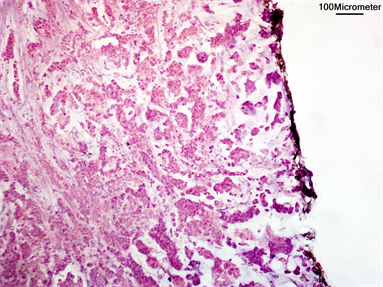

The intraoperative frozen section analysis of safety margin was negative from the start in 183 (83.6%) patients, while it was positive in 36 patients (16.4%) (Figure 2 & Figure 3). Intraoperative decision of margin re-excision was applied for 29 patients (13.2%) in order to reach negative margin, modified radical mastectomy was offered for 4 patients (1.8%), while nipple sparing mastectomy with immediate breast reconstruction using latissimus dorsi flap was offered for 3 patients (1.4%).

Figure 2. Positive surgical margin in intraoperative frozen section, black line indicate inked margin touched by tumor cells (Hematoxylin & eosin staining, 200x).

Figure 3. Negative surgical margin in intraoperative frozen section, black line indicate inked margin (Hematoxylin & eosin staining, 100x).